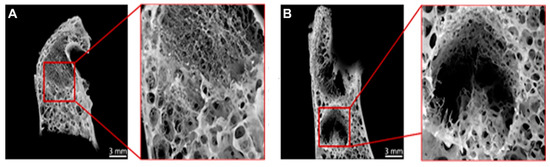

3.2. Radiological Testing Using µCT Showed Impaired Healing of Defect Zone in OVXDS after 8 M

3.3. Impaired Healing in OVXDS Defect Zone Reflects Trabecular Thinning and Failed Fractured Callus Mineralization